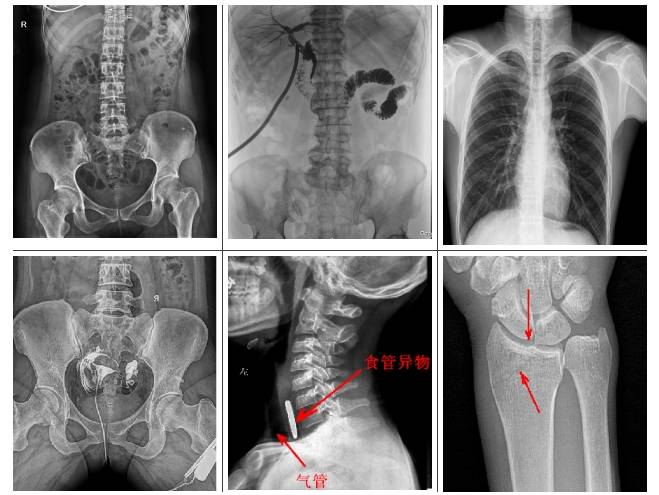

懸吊雙板DR是集拍片、造影于一體,可檢查多類(lèi)疾?。?/p>

1.可檢查患者的呼吸系統(tǒng)疾病,比如是否有肺炎、肺腫瘤、肺結(jié)核、肺膿腫、胸腔積液以及氣胸等。

2.可檢查縱隔以及心臟系統(tǒng)的疾病、骨關(guān)節(jié)系統(tǒng)的疾病。

3.可做泌尿系統(tǒng)造影,子宮輸卵管造影、胃腸道造影,比如做鋇餐的檢查,觀察胃腸道是否有炎癥、腫瘤以及潰瘍等。

4.有職業(yè)病體檢篩查塵肺病功能,及發(fā)現(xiàn)區(qū)別肺部小結(jié)節(jié)功能。